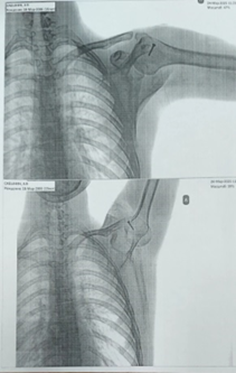

Послеоперационный период протекал без особенностей, конечность иммобилизована косыночной повязкой. На рентген-контроле расположение головки в плечевом суставе корректное, в головке плеча проецируется фиксатор, в качестве которого использован кортикальный винт диаметром 3,5 мм, длиной 25 мм (рис. 4). Иммобилизация осуществлялась повязкой Дезо в течение двух недель. Активные движения в плечевом суставе разрешены через 2 недели после операции.

Рис. 4. Рентгенограмма левого плечевого сустава в послеоперационном периоде. Головка левой плечевой кости в суставной впадине

Примечание: составлен авторами на основе рентгенологического исследования левого плечевого сустава